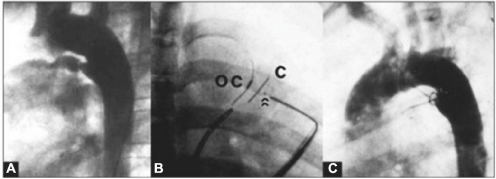

Na figura abaixo, observa-se uma oclusão de canal arterial. A: Canal arterial calibroso do tipo D; B: A imagem em oblíqua anterior direita mostra o dispositivo abotoado antes da liberação. As setas indicam o botão do oclusor abotoado no contra-oclusor; C: Aortografia de controle, demonstrando ausência de fuga residual.

Qual alternativa apresenta o dispositivo de oclusão utilizado.